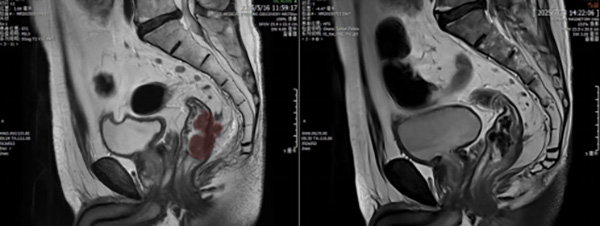

核磁显示放疗后(右)较放疗前(左)肿瘤(红色区域)退缩明显